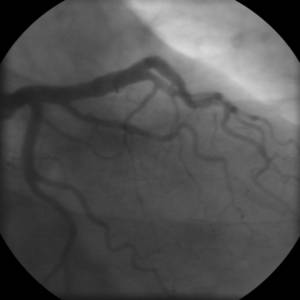

WHAT IS CORONARY ANGIOGRAPHY ?

Coronary angiography is an X-ray examination of the blood vessels of the body brain, kidneys or chambers of the heart. A very small tube (catheter) is inserted into a blood vessel in your groin or arm so as to determine whether the vessels are diseased, narrowed, enlarged or blocked altogether. The tip of the tube is positioned either in the heart or at the beginning of the arteries supplying the heart or any other body part, and a special fluid (called a contrast medium or dye) is injected. This fluid is visible by X-ray, and the pictures that are obtained are called angiograms.

- Show the extent and severity of atherosclerosis in the coronary arteries.

WHAT IS THE INTERPRETATION OF THE FINDINGS OF AN ANGIOGRAM?

An angiogram reveals the location of the blockage and its extent for each vessel of the tested area. The doctor after study of the findings will explain to you or your relatives about the results and future course of action for you. He may opt for any of the following:

- In case the blockages are minimal- below 50% you may be advised to carry on taking prescribed medicines and periodic evaluation along with necessary precautionary measures.

- You may have blockages in 1 or 2 arteries and the size of the same may also be reasonably small. In this case, you will be advised to undergo ANGIOPLASTY with or without stenting.

- In the event of your having multiple blockages or very long lesions in 1 or more arteries which cannot be treated with Angioplasty, you will be advised to undergo Coronary Bypass Grafting Surgery (CABG)